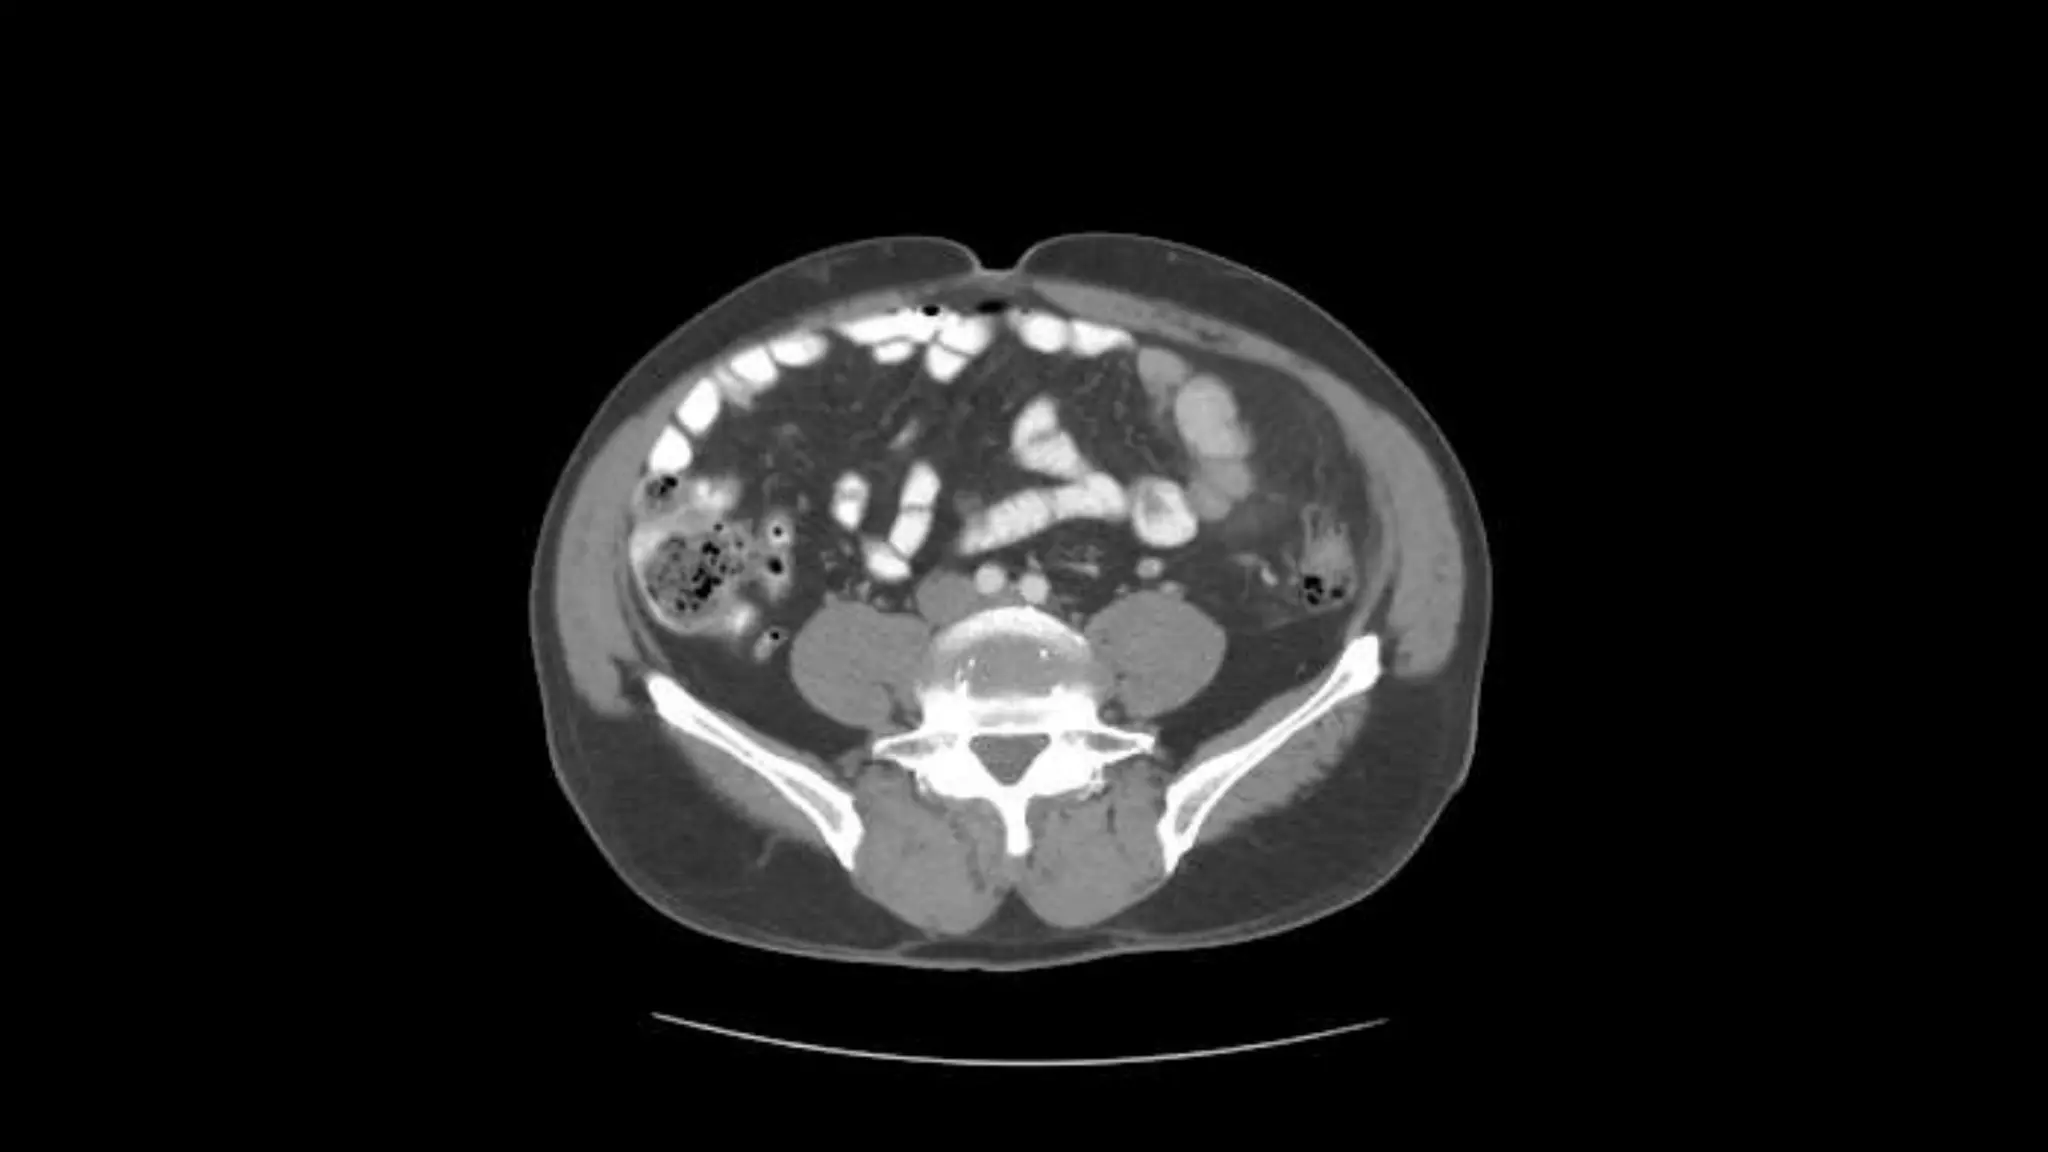

Aorta bifurcates into common illiac arteries

Appendix is noted coiling in Rt. Lower quadrant

Note air in lumen on adjacent scans

Psoas

muscles